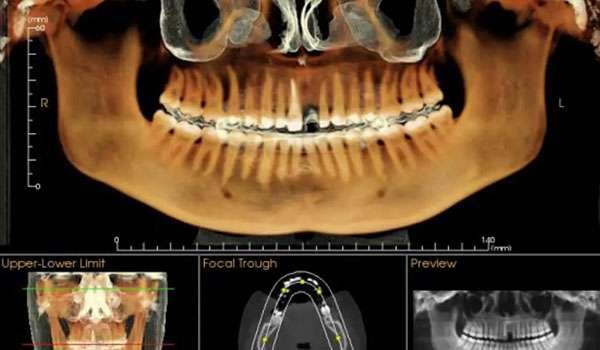

CBCT (Cone Beam Computed Tomography) is a specialized type of X-ray equipment used when regular dental or facial X-rays are not sufficient. It uses a cone-shaped X-ray beam to create detailed 3D images of the bone, soft tissues, nerve pathways, and dental structures in a single scan. This technology is particularly useful for evaluating complex cases and planning surgical procedures.

At The Dental Cure, we pride ourselves on offering innovative dental solutions to ensure our patients receive the best care possible. Among our state-of-the-art services is Cone Beam Computed Tomography (CBCT), a groundbreaking imaging technology that provides detailed, three-dimensional images of the bone and surrounding structures. This advanced imaging technique significantly enhances our diagnostic capabilities and treatment planning, ensuring optimal outcomes for our patients.

3. Image Processing: The captured images are compiled to create a comprehensive 3D representation of the scanned area. This detailed view allows our dentists to accurately assess your dental and bone structures.

• Detailed 3D Imaging: Provides a complete view of the bone, teeth, and soft tissues, enabling precise diagnosis and treatment planning.

• Improved Treatment Planning: Facilitates the planning of dental implants, orthodontic procedures, and other surgical treatments with high precision.